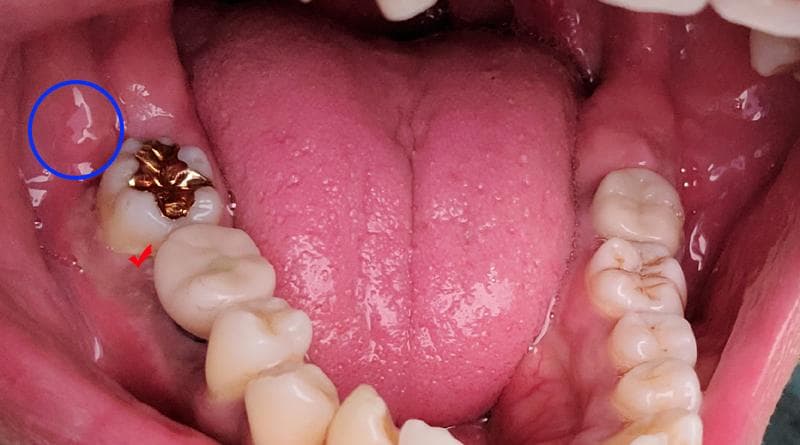

8/25일 통증이 생겼고 처음에 사진상 빨간 체크부위가 아파서 내원했습니다. 이후 9월1일부터 지금까지 잇몸치료(미노클린주입) 2회 -> 임플란트 상부보철물제거 -> 9월20일 인레이치아 부터 뒤쪽 잇몸까지 절개 소파술 시행 하였습니다. 현재는 저 부위에 통증은 사라진 상태지만 통증이 이동하여 파란동그라미 부위에 통증이 생겨 현재도 약을 복용하고 있습니다. 큰통증은 잡혔지만 아직도 통증의 원인을 모르겠습니다.

• 1번 째 사진